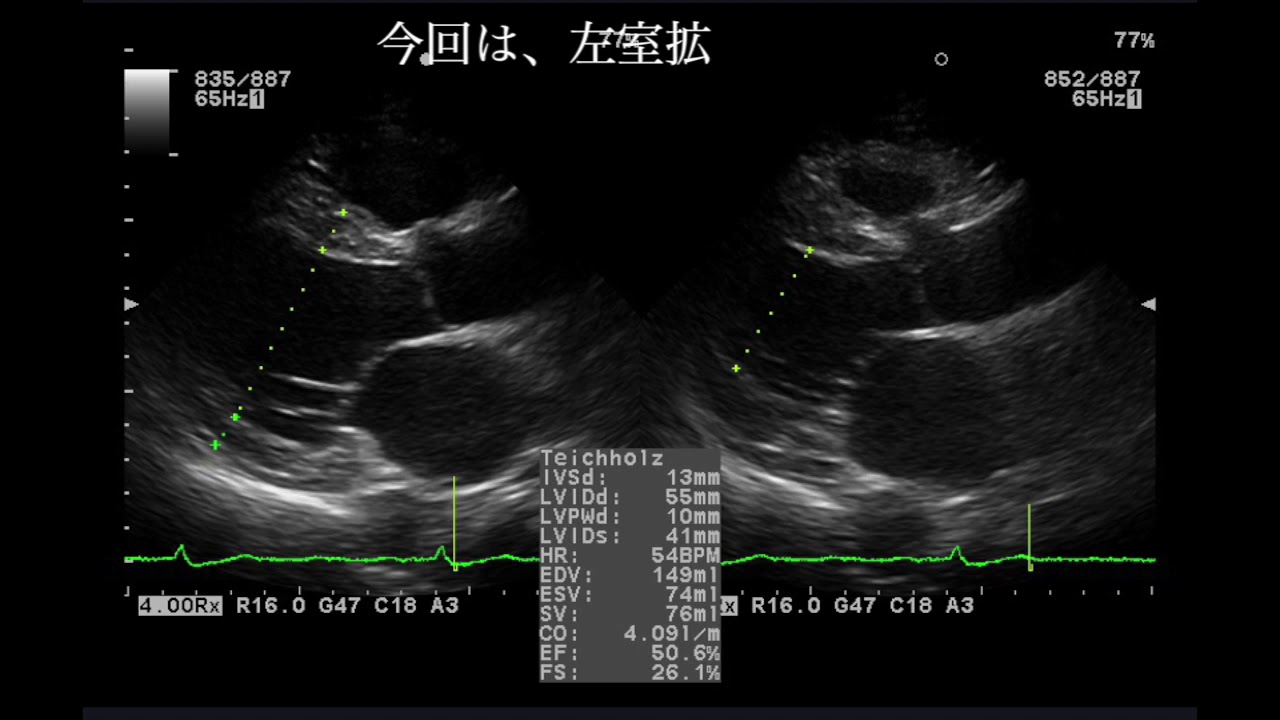

画像検査はHCMの診断の特徴です。医療専門家は、次のようないくつかのことを測定するためにさまざまな検査を実行することがあります。

- 心筋の厚さと肥大

- 僧帽弁閉鎖不全症

- 心臓の動きと心拍数

- 心臓が送り出す血液の量